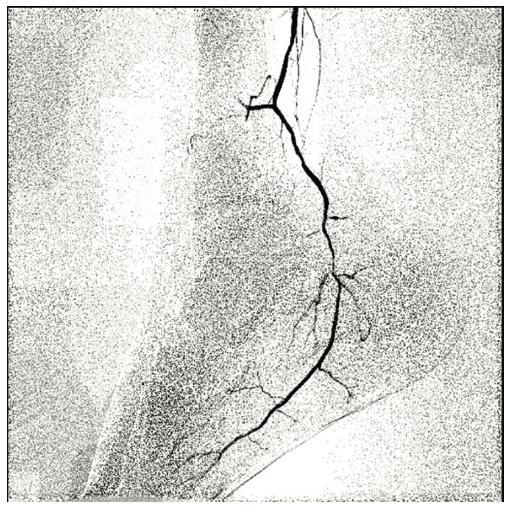

A 6 French (Fr) sheath was inserted into the right femoral artery in an antegrade fashion. An .035-inch x 90 cm Trailblazer (Medtronic) was inserted over an .035-inch x 180 cm Aquatrack guidewire (Cordis, A Cardinal Health company) and advanced into the right popliteal artery. Angiography was performed prior to surgical cut down of the posterior tibial artery (PT) (Figure 1). Access into the PT was made using a 4 Fr micropuncture pedal sheath (Cook Medical). An .014-inch Confianza guidewire (Asahi Intecc) was inserted and advanced into the PT. Using the stiff Confianza, a Viance Flexible CTO catheter (Medtronic) was advanced. When Viance extravasated from the PT, an Aquatrack wire and .035-inch Trailblazer were introduced and advanced in a antegrade manner. The Viance and Trailblazer could be visualized going in different directions (Figure 2). Using that image, the Viance was pulled back and repositioned to find the true lumen from the bottom to the top, using the guidance from the wire. The Confianza was readvanced after the true lumen was found, and Aquatrack was pulled back into the Trailblazer and eventually removed. The Confianza wire was advanced further into the .035-inch Trailblazer, and eventually pulled through the right femoral artery sheath in a retrograde fashion (Figure 3). The right femoral artery Trailblazer was removed. A TurboHawk SX-C atherectomy catheter (Medtronic) was used to debulk the plaque and achieve luminal gain from the popliteal artery into the tibioperoneal trunk (Figure 4). Drug-coated balloon angioplasty was performed using the IN.PACT balloon (Medtronic) into the popliteal artery (Figure 5). The TurboHawk was reinserted and advanced further down to the peroneal artery into the tibioperoneal trunk in order to establish luminal gain in the distal vessel. Final angiography revealed successful recanalization of the lower extremity vessels through the use of the antegrade/retrograde method, with distal access through the posterior tibial artery (Figure 6).